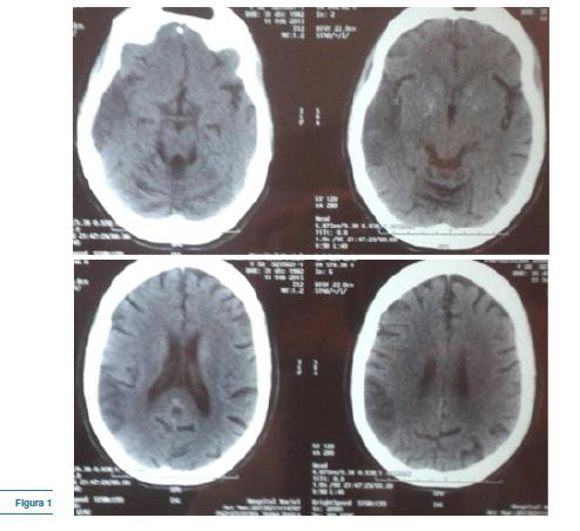

Con el planteo de encefalitis infecciosa en primer lugar y de accidente cerebro vascular (ACV) febril en segundo, se realiza una tomografía (TC) cráneo donde se aprecia un área hipodensatémporo-parietal derecha y calcificaciones gangliobasales (figura 1).

Los eventos focales de tipo ACV debutan característicamente antes de los 15 años y usualmente antes de los 40 años (2). Como se aprecia en la neuroimagen de la paciente, los mismos no respetan territorios vasculares arteriales y predominan en la topografía parieto-occipital. (1,2) El hallazgo de calcificaciones gangliobasales también es característico, así como el signo del pulvinar bilateral, el cual además de la MELAS, también puede verse en la enfermedad de Fabry, el sindrome de Wernicke-Korsakoff y la enfermedad de Creutzfeldt-Jakob. (4)